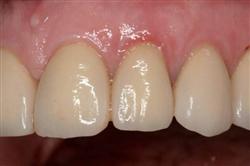

Cosmetic Soft Tissue Grafting

In addition to the functional problems previously mentioned, receding gums can look unsightly.

Longer looking teeth and exposed tooth roots give an "old" appearance to your smile. Some people cover their mouths when they smile for this very reason.

Cosmetic Soft Tissue Grafting can add a new youthful appearance to your smile. In your initial consultation with Dr. Hoidal, he will thoroughly explain what can be achieved in your particular case.